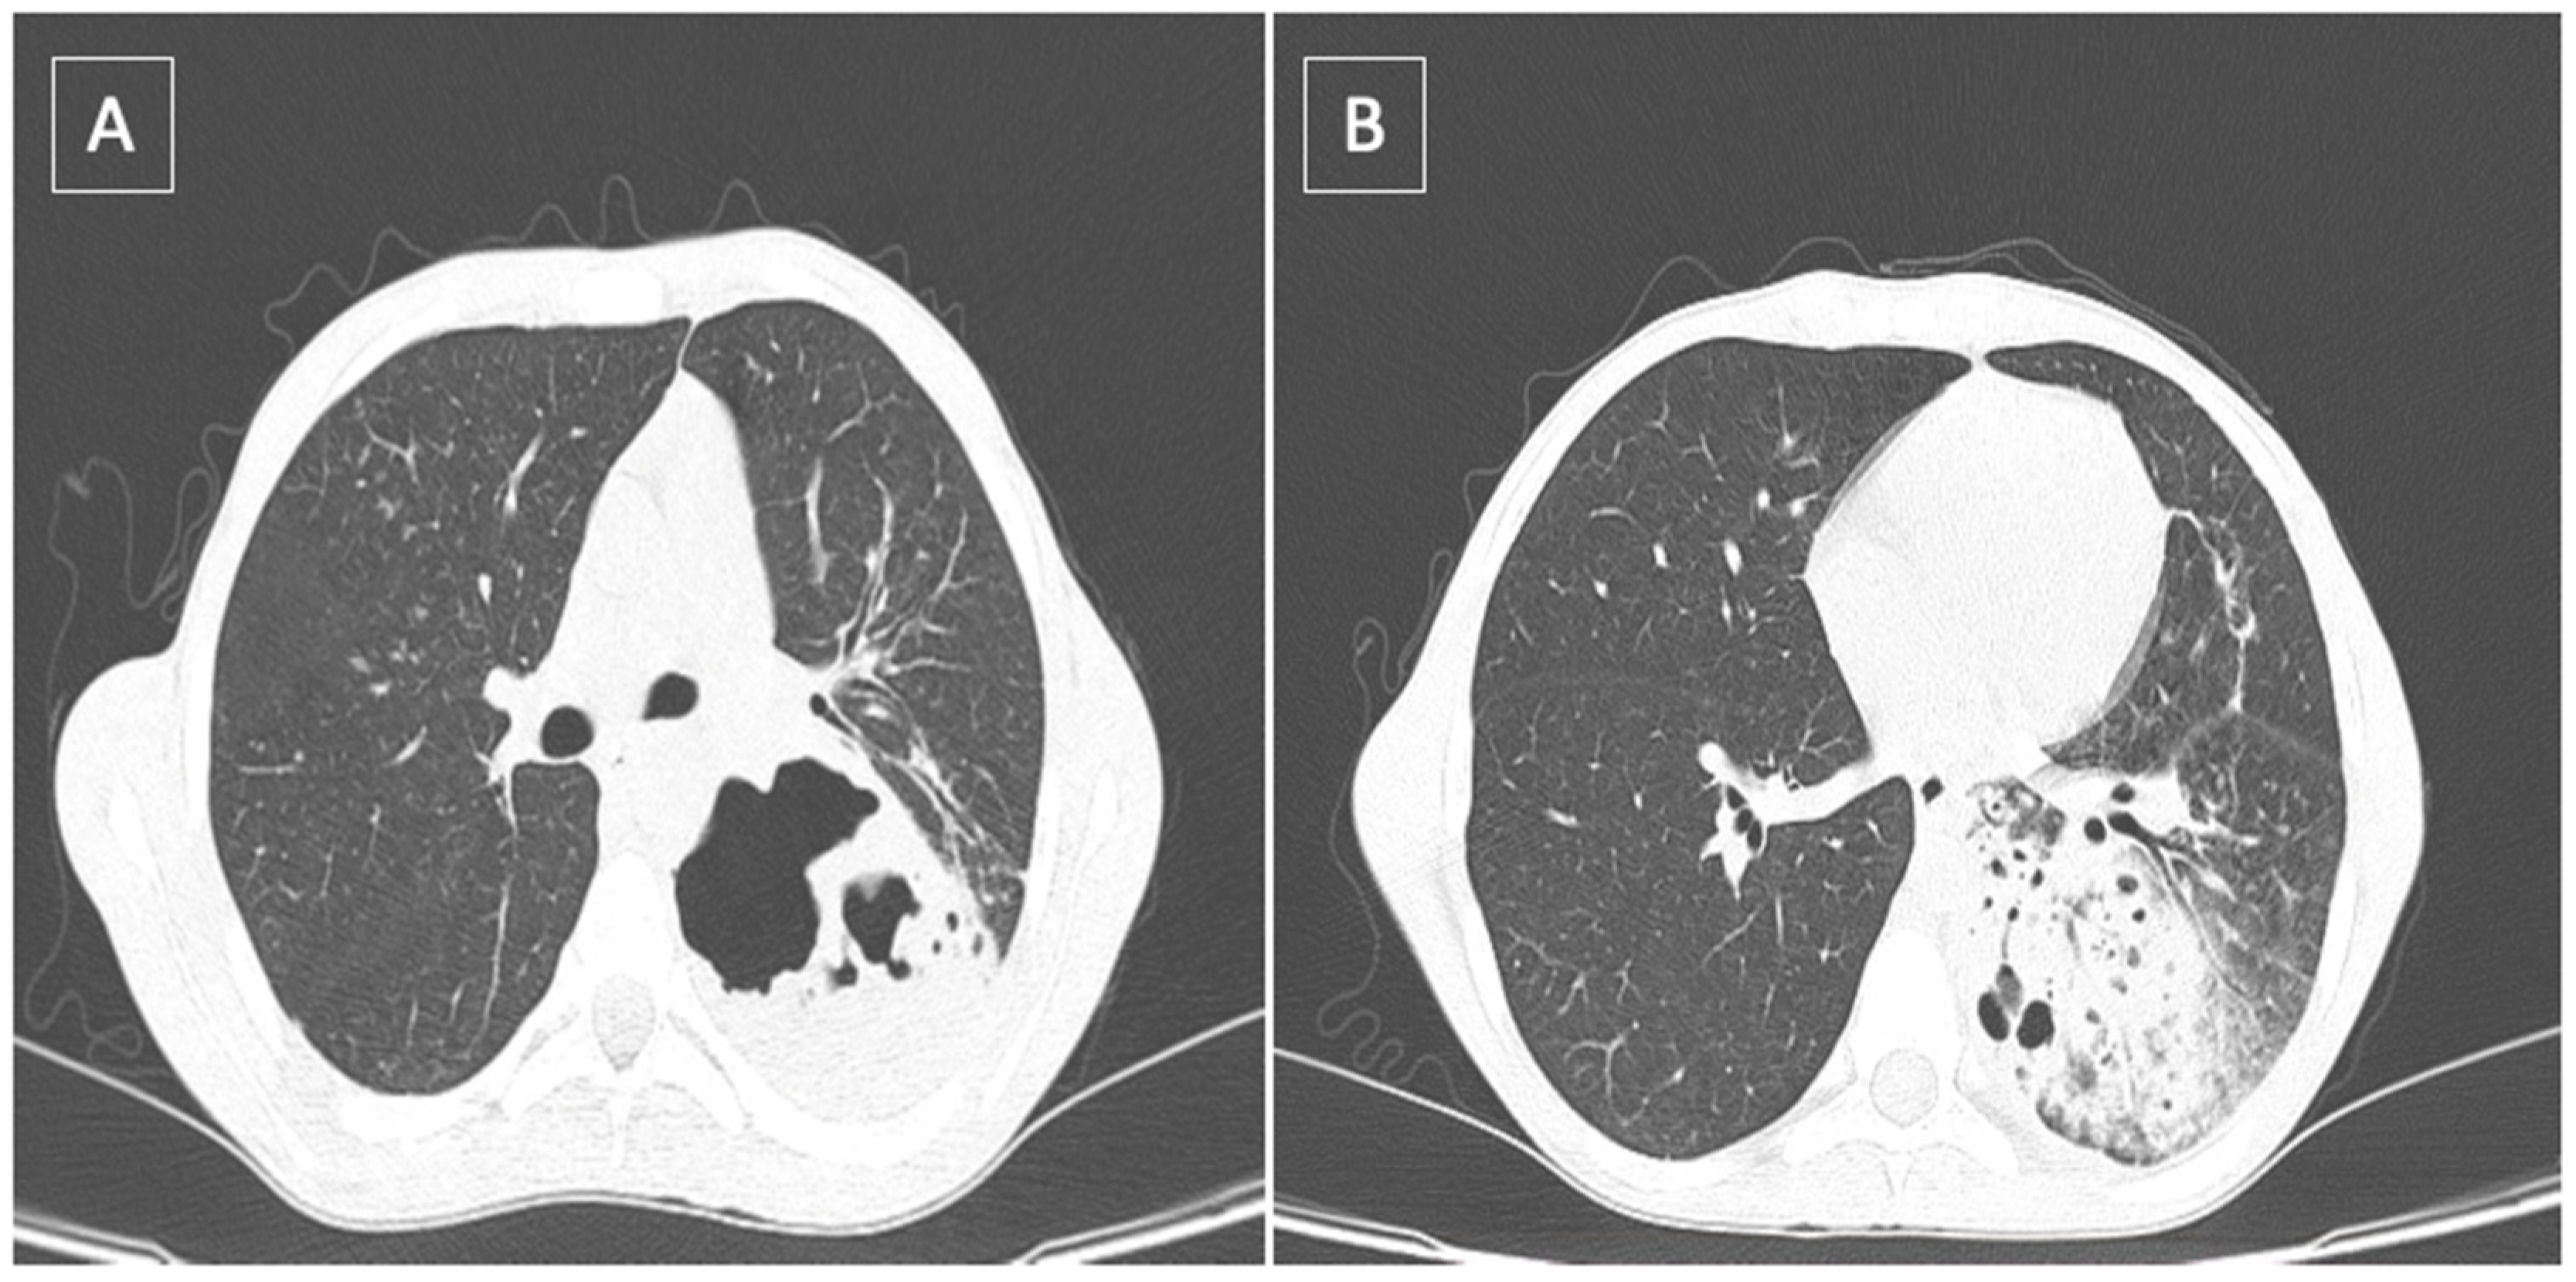

2. Case Report